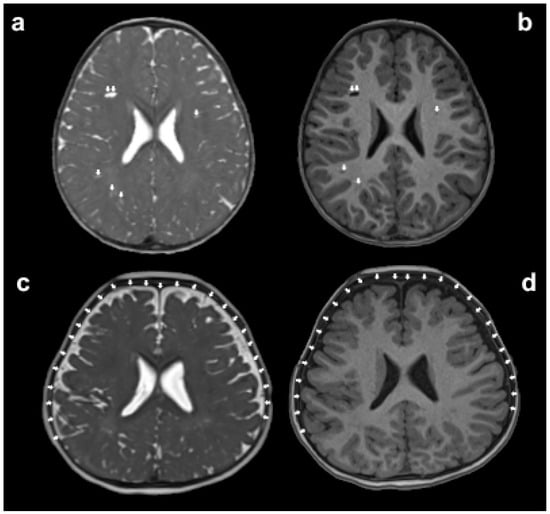

Figure 3.

The assessment of glymphatic system disorders can be indirectly made by observing whether there is an enlargement in the volume of paravascular spaces (PVS) and extra-axial cerebrospinal fluid (EA-CSF) on magnetic resonance imaging (MRI). The white arrows in panels (a,b) indicate the enlarged PVS, while the white arrows in panels (c,d) point out the increased volume of EA-CSF.